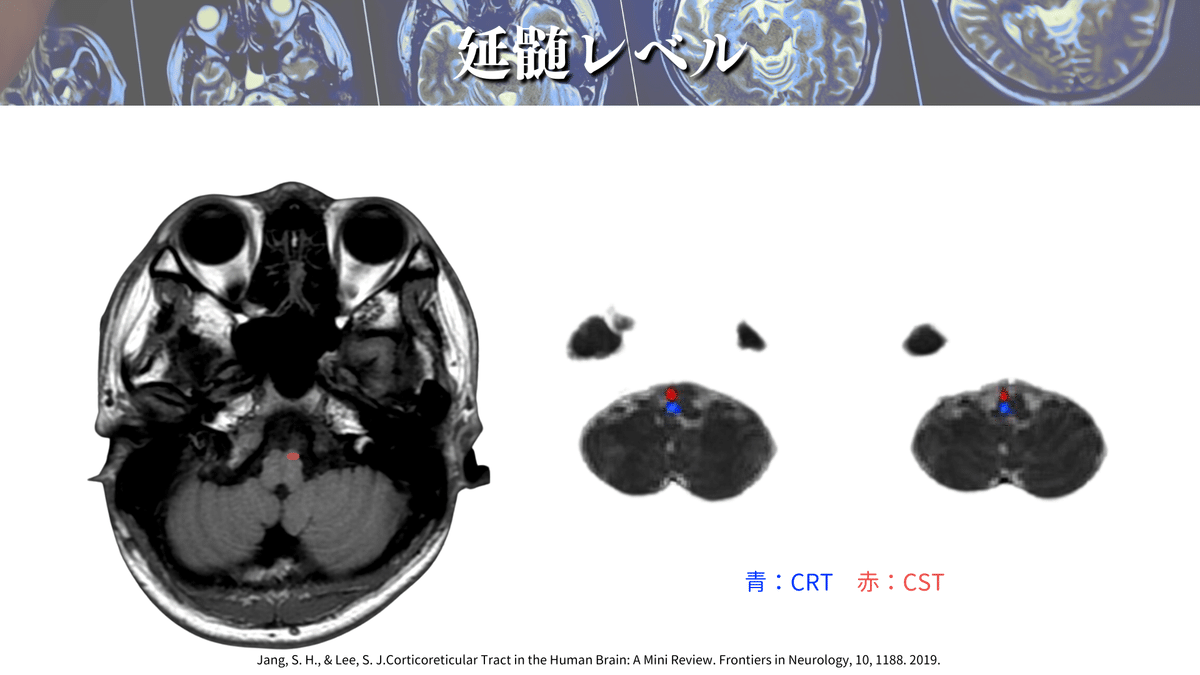

延髄レベル

詳しい場所も見ていきましょう!

CSTはよく「錐体路」と言われていますが、これはこの延髄錐体を通過するからになります👍

この錐体を通過する際に対側に交叉するので、脳とは反対側の四肢の運動を制御しているわけですね‼️

DTTで確認してみても、前方の延髄錐体を通過していることが分かりますね👍

ちなみに、延髄錐体で交叉をするわけですが、錐体交叉後に損傷された場合には損傷側と同側の運動麻痺が出現しますので、損傷レベルには注意してくださいね🙇♂️

Jang, S. H., & Lee, S. J.(2019).Corticoreticular Tract in the Human Brain: A Mini Review. Frontiers in Neurology, 10, 1188.